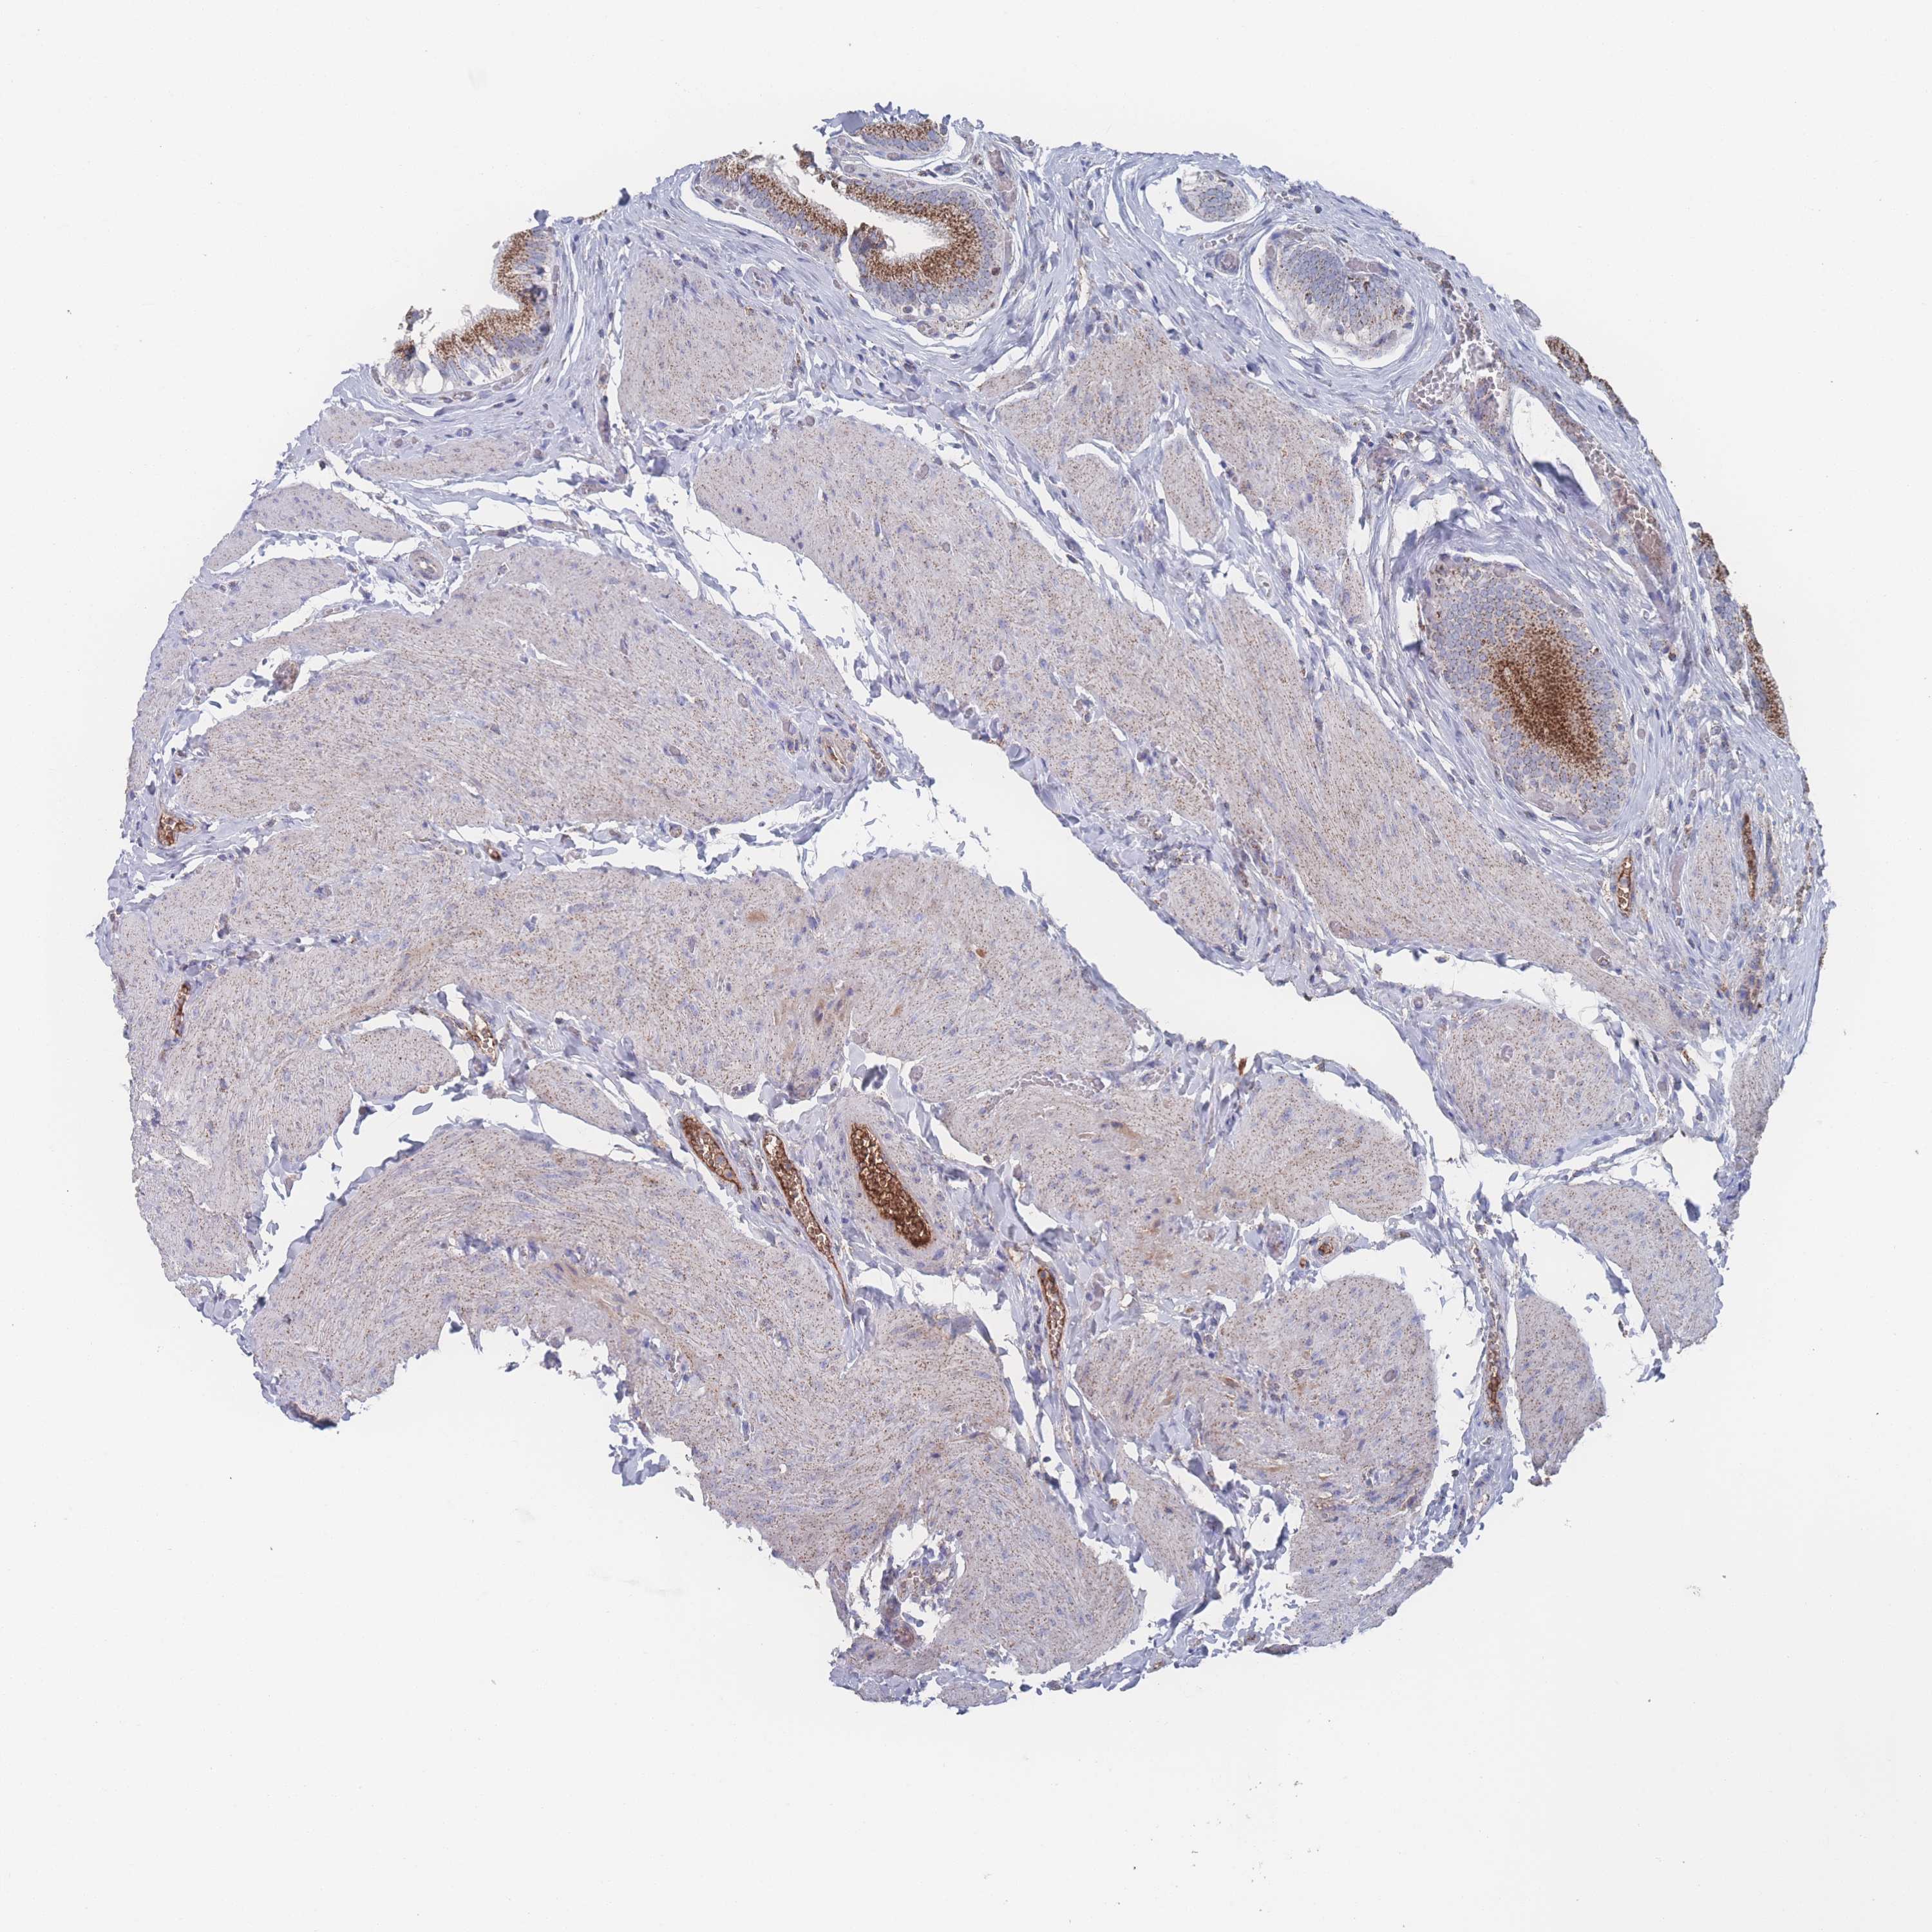

PEX14